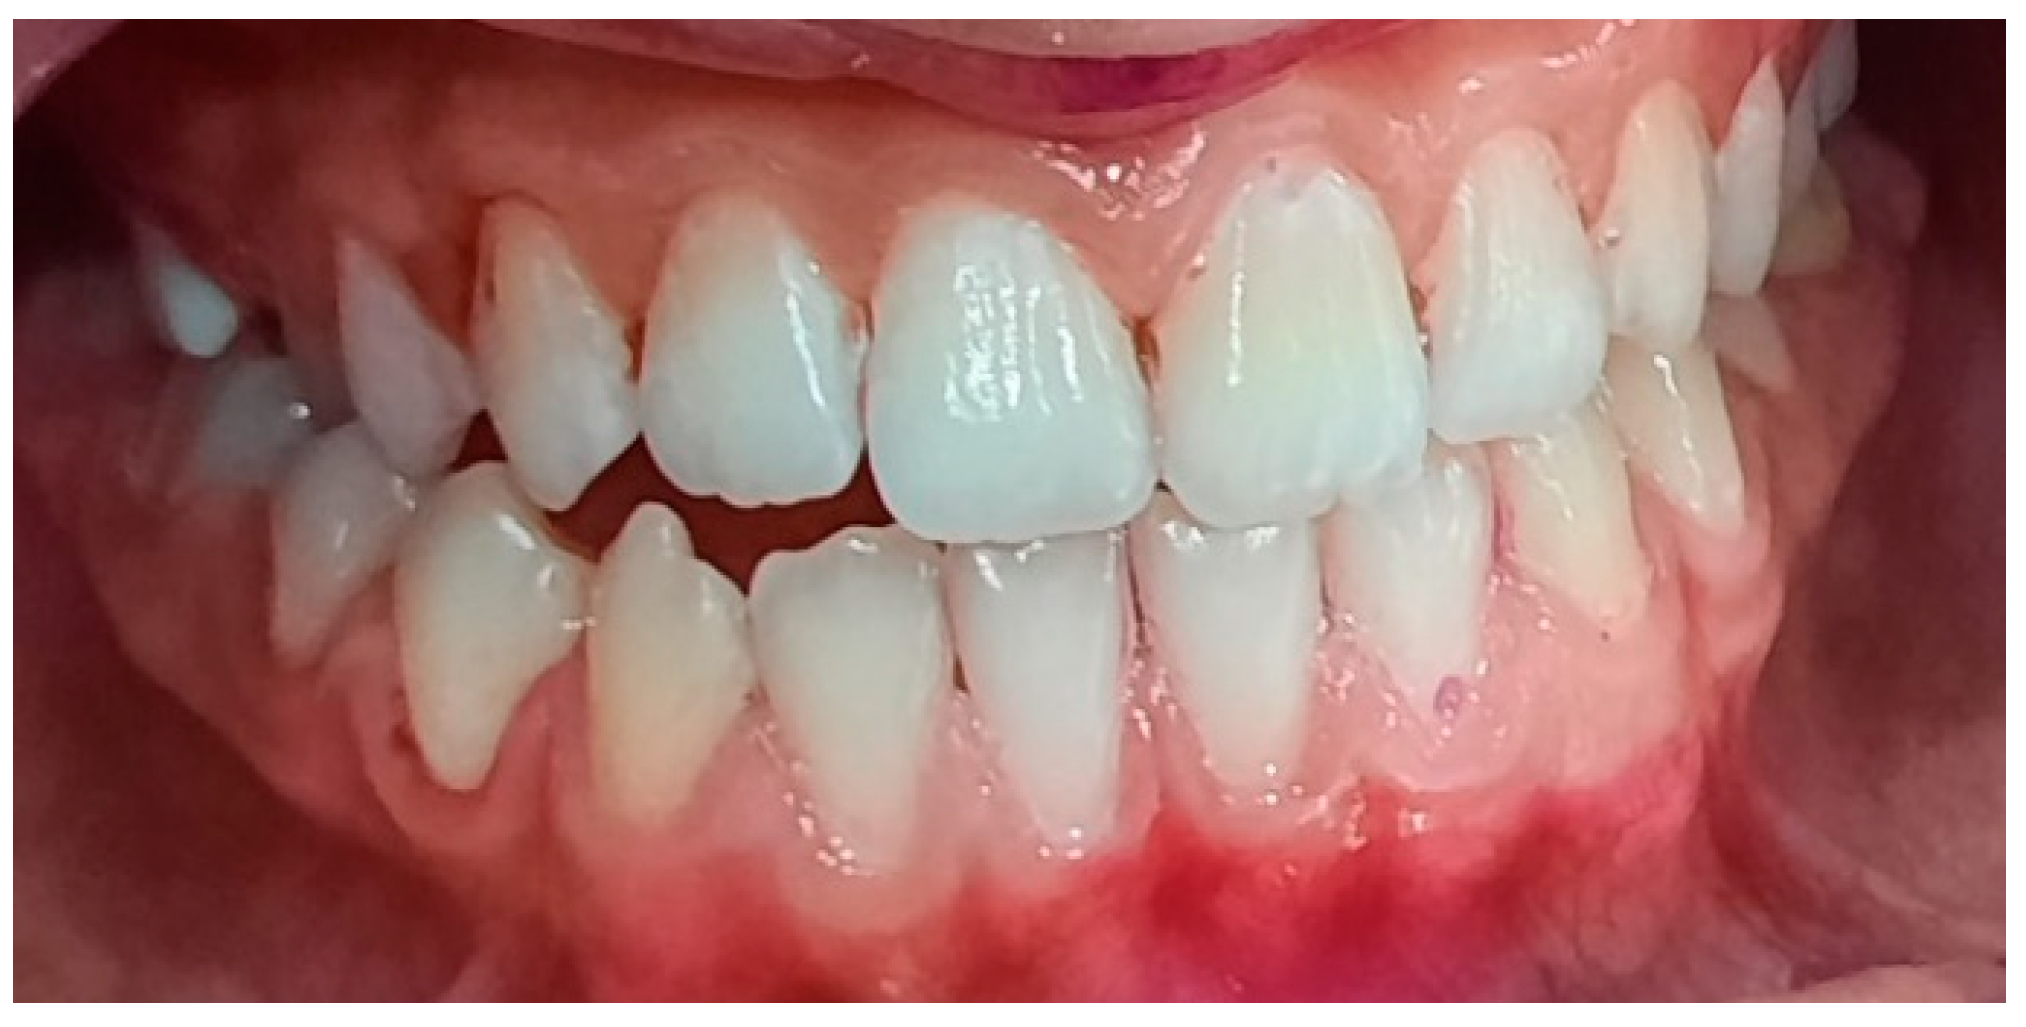

2.2. Clinical Examinations

3.2. Analysis of Clinical Data